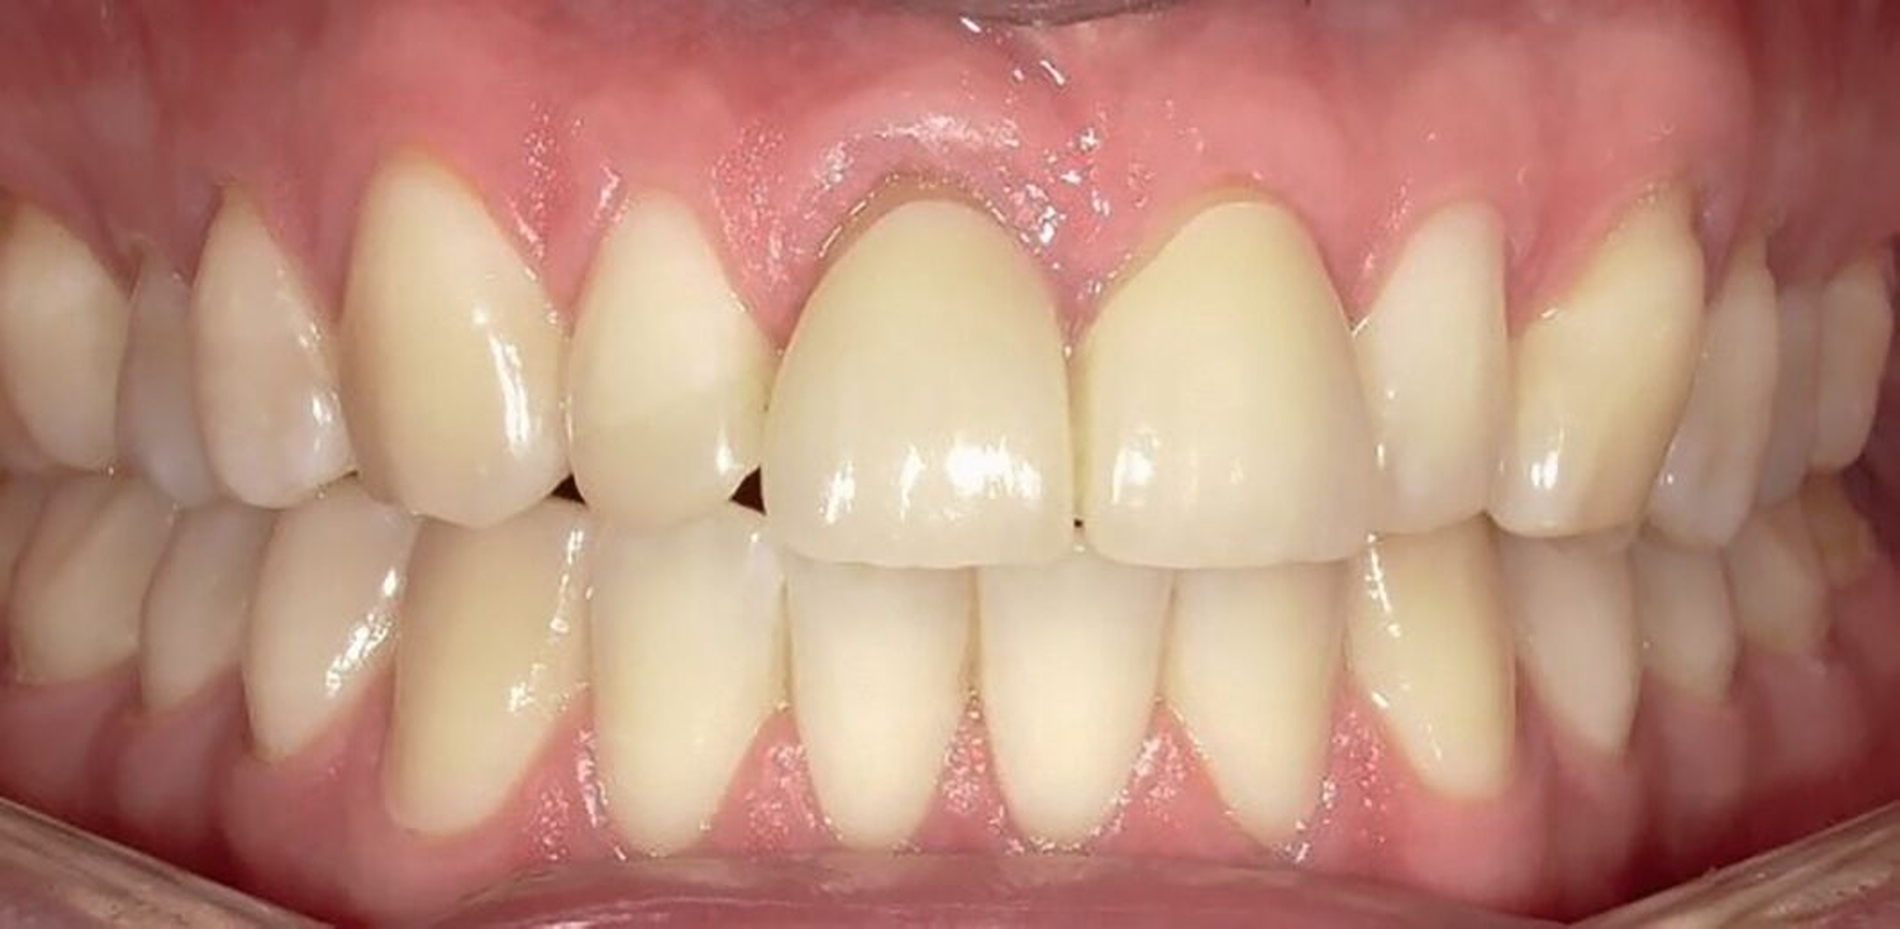

Ein 22-jähriger Patient stellte sich im Februar 2020 im zahnärztlichen Notdienst der Klinik für Zahn-, Mund- und Kieferkrankheiten Mainz vor. Aufgrund einer Synkope war er mit dem Oberkiefer auf den Rand einer Badewanne gestürzt. Intraoral zeigte sich der Zahn 12 mit einer Schmelz-Dentin-Fraktur ohne Pulpabeteiligung (unkomplizierte Kronenfraktur), der Zahn 11 mit einer Kronen-Wurzel-Fraktur mit Pulpabeteiligung und der Zahn 21 mit einer Schmelz-Dentin-Fraktur mit Pulpabeteiligung (komplizierte Kronenfraktur). Die Zähne zeigten keine erhöhten Lockerungsgrade oder Dislokationen (Abbildung 2). Herausfordernd für die weitere Versorgung war der Frakturverlauf an Zahn 11, an dem die Frakturkante palatinal tief subgingival und mesio-palatinal auch subkrestal lag. Röntgenologisch konnte die klinisch gestellte Verdachtsdiagnose bestätigt und eine Wurzelfraktur ausgeschlossen werden (Abbildung 3).